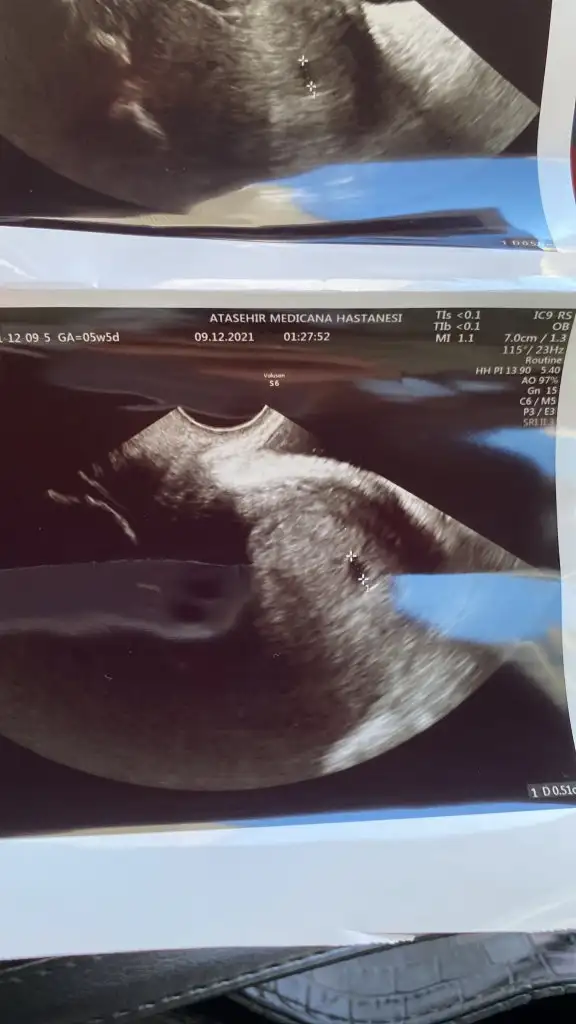

Çıktım kızlar. Dış gebelik ihtimali yok kese yerleşmiş ama düşük kanamasıda olabilir yerleşme kanaması da olabilir dedi iğne yaptı progestan verdi hcg takibine gerek yok daha neler dedi. Bol dua bol dinlenme

Selam kızlar bende ağustos annesi olacağım inş ama benim geç döllenmeninde geç döllenmesi olduğu için Kaç haftalık hamileyim bilmiyorum pazar günü keseyi gördüm 5,08 mm di cumartesi randevum var inş kese büyümüştür ve yolk saç görünür Sat 16 ekim ama şu an 5 haftalık falan hamileyimdir sanırım